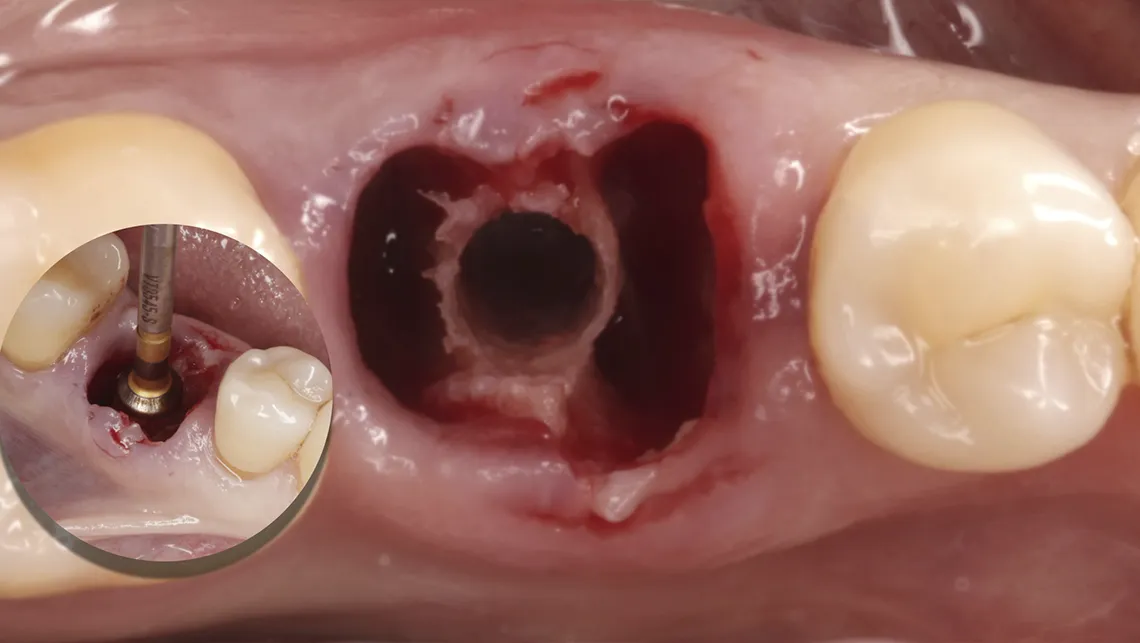

Fig. 13.  Fotografía del control de estabilidad biológica con sistema Osstell, tras la instalación de un implante postextracción Galimplant con oseodensificación

La oseodensificación también ha ampliado las posibilidades de la implantación inmediata, especialmente en la región molar. Mediante la expansión del tabique interradicular, es posible lograr una estabilidad primaria adecuada incluso en alvéolos complejos, siempre que se respeten criterios biomecánicos mínimos, como un torque de inserción suficiente.

Asimismo, la técnica SPOT (Selective Preservation of Tooth) representa una evolución del concepto de Socket Shield, al estandarizar la preparación del escudo radicular y la osteotomía mediante oseodensificación. Este enfoque permite preservar tejidos duros y blandos, mejorar la estabilidad primaria y optimizar la cicatrización temprana (figura 18).